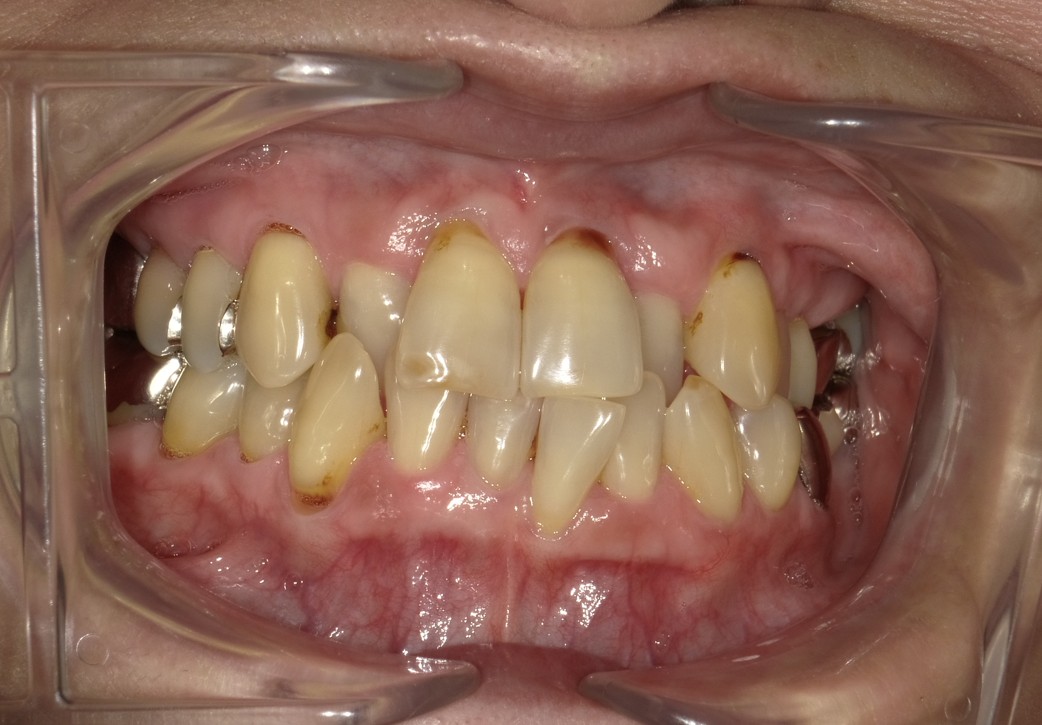

上下のガチャ歯を改善した1症例

治療前 ![]() |

上の歯と下の歯が前後しているのが気になる |

骨格 軽度Ⅲ級 |

今回は即切歯が交叉咬合の一症例です。 |